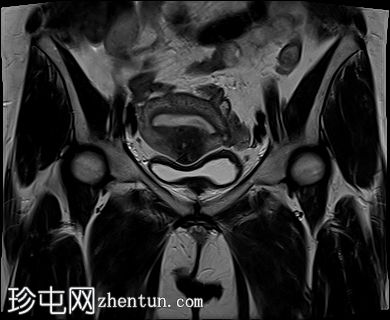

矢状位

T2加权像

子宫前壁交界区局灶性增厚,边界不清。形成直径约3厘米的局灶性肿块样病变,轻度压迫膀胱。肿块边界模糊不清,可见多个细小出血灶,在T1加权像和T2加权像上均呈高信号,提示局灶性子宫腺肌症。

子宫体前壁可见另一处病灶,位于上述病灶尾侧,边界清晰(有包膜)。该病灶在T1和T2加权像上均呈低信号,内部未见异常信号灶,周围可见少量明显血管通道,提示为小型子宫肌瘤。

子宫内膜厚度正常。

宫颈MRI表现正常,可见少量纳博氏囊肿。

边界模糊不清是局灶性子宫腺肌症(无包膜)的特征。此外,病灶内存在多个微小的内部出血灶(异位腺体),且邻近增厚模糊的交界区,这些都是局灶性子宫腺肌症的诊断标准。

在上述病灶尾侧可见另一处具有不同影像学特征的病灶,该病灶边界清晰(有包膜),且信号均匀(无微小的内部出血灶),提示可能合并子宫肌瘤。